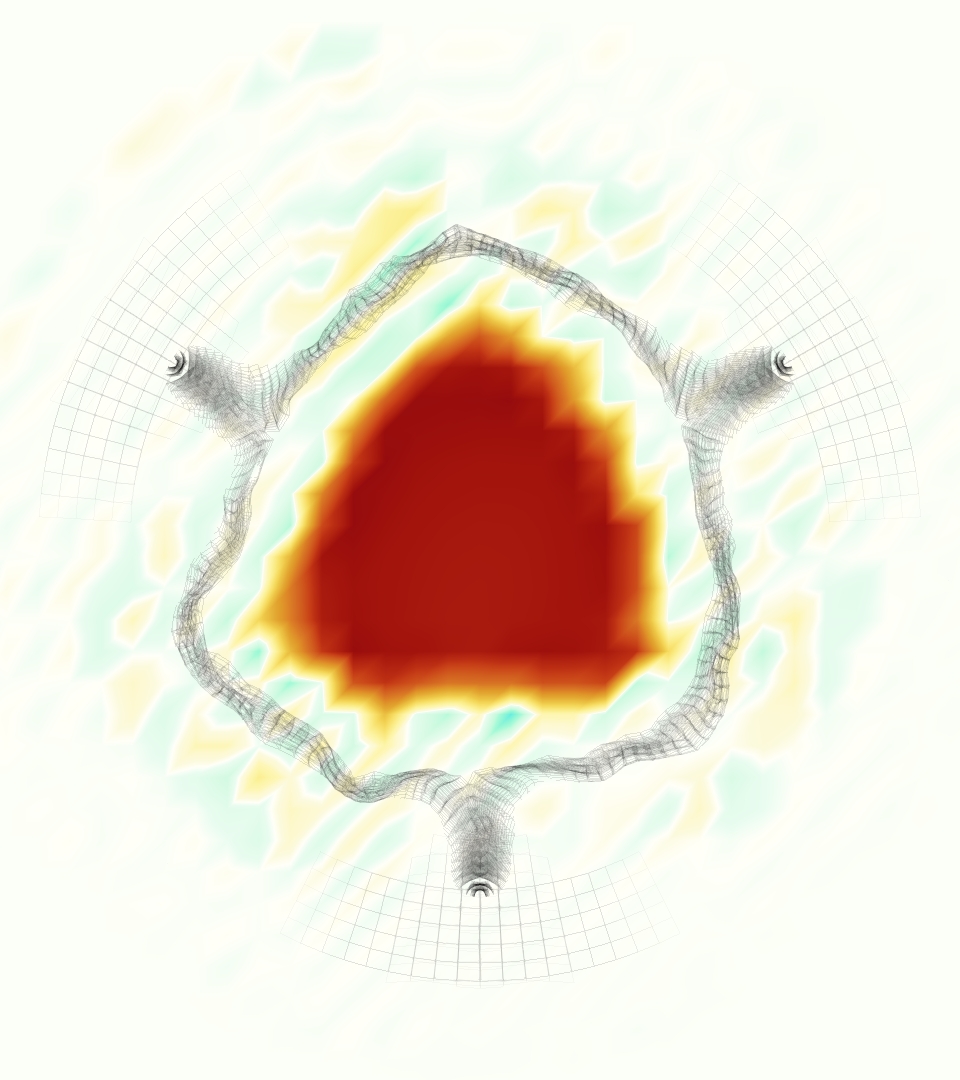

At = 0, the axial slice directly at the valve annulus shown in columns 1 and 2 in Figure 6, there was excellent agreement between the simulation and experiment over the cardiac cycle in the speed and shape of the jet through the valve. In both cases, the axial velocity increased as the flow accelerated during systole and the valve leaflets opened, then decreased during diastole with slight negative velocity before the valve leaflets were fully closed. The forward flow through the valve annulus did not form a full circle, but rather developed a triangular shape with a point of the triangle forming along the interior curve of the vessel, at the bottom of the axial slices. At = 0, the points of this triangular jet shape aligned with the commissures of the valve. This shape persisted during peak systole and was well-matched by the simulation.

The axial slice = 0.625 cm, shown in columns 3 and 4 in Figure 6, cut through the support scaffolding of the valve and the leaflets when they are open. In the experimental data, the shape of the jet changed as it moved downstream. A triangular shape occurred, but the points were then aligned with the middle of each open leaflet as opposed to the commissures. Those points were also more rounded than they were at = 0. The peak velocity of the jet was faster at = 0.625 cm than at = 0, as the flow accelerated through the open valve leaflets. The simulation produced these features at = 0.625 cm. The triangular shape of the jet shifted similarly, and its speed increased compared to the upstream slice. As the flow decelerated into diastole, the jet shape remained roughly triangular but diminished in intensity before disappearing after valve closure.

The jet continued to develop at = 1.25 cm, an axial slice immediately downstream of the valve scaffolding and open leaflets, shown in columns 5 and 6 in Figure 6. In the experimental data, the points of the triangular jet shape extended further towards the vessel wall. In addition, regions of reversed flow developed in the locations downstream of the commissures, resulting in curved sides to the shape of the jet. Each tip of the jet was unique, due to variations in the individual leaflets in the physical bioprosthetic valve. These variations are apparent in the velocity fields, possibly because the jet edges are similar enough cycle to cycle that irregularities are still being captured even with phase averaging. Further discussion of these features can be found in Schiavone et al. [39], which showed that the jet tip shapes occurred in different pulmonary anatomies, demonstrating that they were likely due to inherent properties of each leaflet. The leaflets in the mathematical model of the valve are identical, so these nuances in leaflet variation could not be replicated. The simulation did capture some of the extension of the tips of the jet, as they were closer to vessel wall at slice = 1.25 cm than = 0.625 cm. The curves in the triangular sides of the jet were also present in the simulation, though they were less pronounced than the experimental data. At both = 0.625 cm and = 1.25 cm, the jet shape in the simulation was smoother than the jet in experiment. It is possible that the free edges of the leaflets in the mathematical model are not fully replicating the behavior of the physical leaflets of the bioprosthetic valve, in particular the amplitude or frequency of leaflet flutter, leading to the variations seen in the jet shape at = 1.25 cm downstream of the leaflet edges. The simulation, however, does capture the key features of the triangular shape and speed of the jet. Overall, qualitative comparisons demonstrated that the simulation reproduced key features of the flow during systole and diastole.